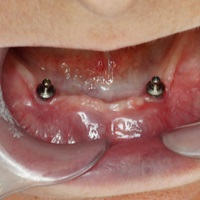

Pacjentka lat 72, od kilkudziesięciu lat chorująca na cukrzyce I typu, obecnie od 10 lat na pompie insulinowej. Profesor medycyny, siostrzenica pacjentki prowadzi swoją ciocię diabetologicznie, pacjentka świadoma zagrożeń przy zabiegach regeneracji kości i implantacji w takim ogólnym stanie zdrowia. Po rekonstrukcji tkanek miękkich i kości osadzono dwa implanty o średnicy 5,0 mm. Na zdjęciu śródzabiegowym widać zadowalające wyniki rekonstrukcji tkanki kostnej. Po upływie kilku miesięcy wykonano nadbudowę protetyczną.